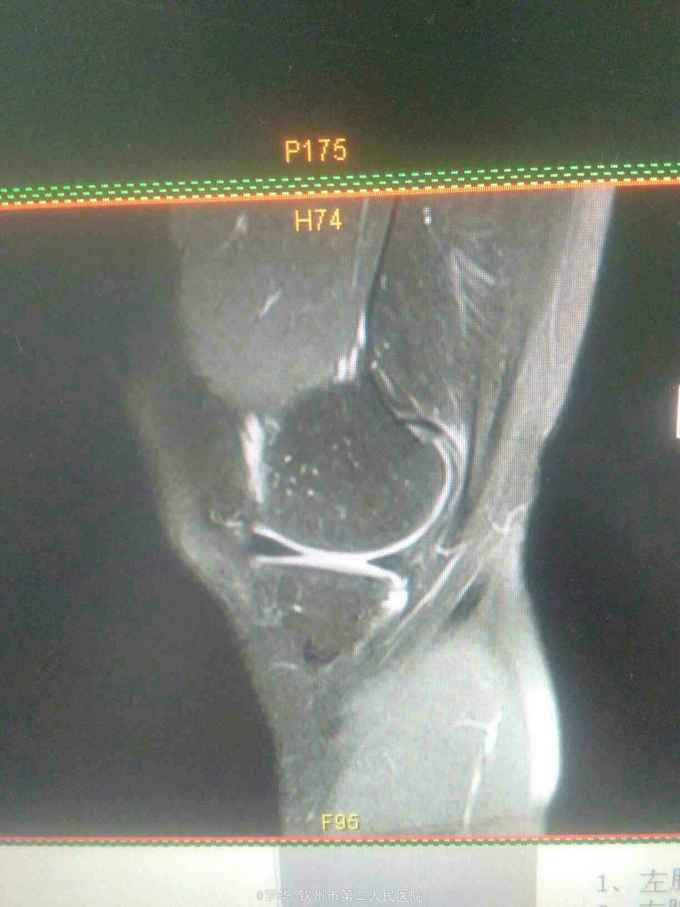

主诉:扭伤致左膝关节活动受限3月余。病史:患者男性,31岁,于入院3月余前扭伤左膝关节,致左膝关节肿痛、活动受限,尚可站立行走,但不能剧烈运动及重体力劳动,曾行磁共振检查提示左膝前交叉韧带损伤,半月板损伤,现为进上一步治疗入院。

查体:左膝关节无明显压痛,前抽屉试验阳性,侧方应力试验、麦氏征、研磨试验均阴性,膝关节屈伸活动可,余查体未见特殊。 辅查:膝关节磁共振提示左前交叉韧带损伤,左膝关节半月板损伤。

诊断:左膝关节前交叉韧带断裂,左膝关节半月板损伤。 治疗:予硬外麻下行左膝关节前交叉韧带重建术。